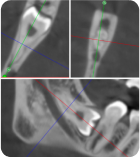

Методика удаления зубов в боковом сегменте верхней челюсти

Что будет в модуле:

Атравматичное удаление премоляров и моляров верхней челюсти

Инструменты и четкие правила удаления

Осложнения: ороантральное сообщение, попадание корня в пазуху

От простого удаления щипцами до фрагментации бором - вы приобретете уверенные навыки в боковом сегменте верхней челюсти, включая работу с осложнениями.